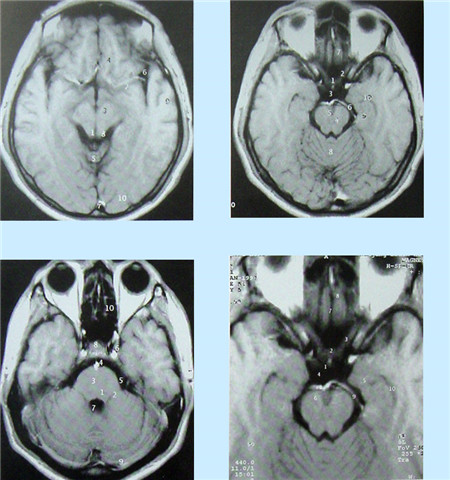

核磁共振血管成像(MRI)簡介

核磁共振(MRI)又叫核磁共振成像技術。是繼CT后醫學影像學的又一重大進步。自80年代應用以來,它以極快的速度得到發展。其基本原理是:將人體置于特殊的磁場中,用無線電射頻脈沖激發人體內氫原子核,引起氫原子核共振,并吸收能量。在停止射頻脈沖后,氫原子核按特定頻率發出射電信號,并將吸收的能量釋放出來,被體外的接受器收錄,經電子計算機處理獲得圖像,這就叫做核磁共振成像。

核磁共振成像無電離,對機體沒有不良影響。MRI對檢測腦內血腫、腦外血腫、腦腫瘤、顱內動脈瘤、動靜脈血管畸形、腦缺血、椎管內腫瘤、脊髓空洞癥和脊髓積水等顱腦常見疾病很有效。

核磁共振成像設備價格昂貴,檢查費用也較高,它與CT都可以提供斷層的靜態掃描圖像。

數字減影血管造影DSA腦血管圖像顯示 核磁共振MRI掃描腦組織圖像